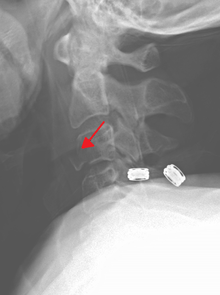

Severe pain will usually be present at the point of injury. Pressure on a nerve may also cause pain from the neck down the shoulders and/or arms. Bruising and swelling may be present at the back of the neck. A neurological exam will be performed to assess for spinal cord injury. X-rays will be ordered to determine the severity and location of the fracture. CT (computed tomography) scans may be ordered to assess for gross abnormalities not visible by regular X-ray. MRI (magnetic resonance imaging) tests may be ordered to provide high resolution images of soft tissue and determine whether there has been damage to the spinal cord, although such damage is usually obvious in the conscious patient because of the immediate functional consequences of numbness and paralysis in much of the body.

Surgery may be needed to stabilize the neck and relieve pressure on the spinal cord. A variety of surgeries are available depending on the injury. Surgery to remove a damaged intervertebral disc may be done to relieve pressure on the spinal cord. The discs are cushions between the vertebrae. After the disc is removed, the vertebrae may be fused together to provide stability. Metal plates, screws, or wires may be needed to hold vertebrae or pieces in place.